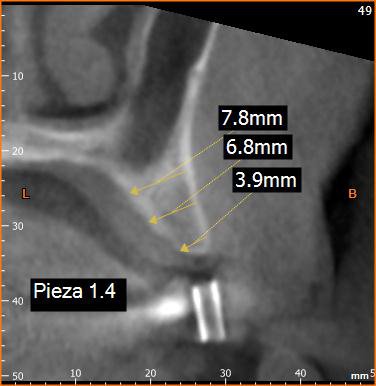

Por medio de la tomografía computadorizada para implantes dentales es posible determinar: